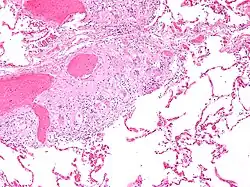

Cuerpo de asteroide en sarcoidosis.